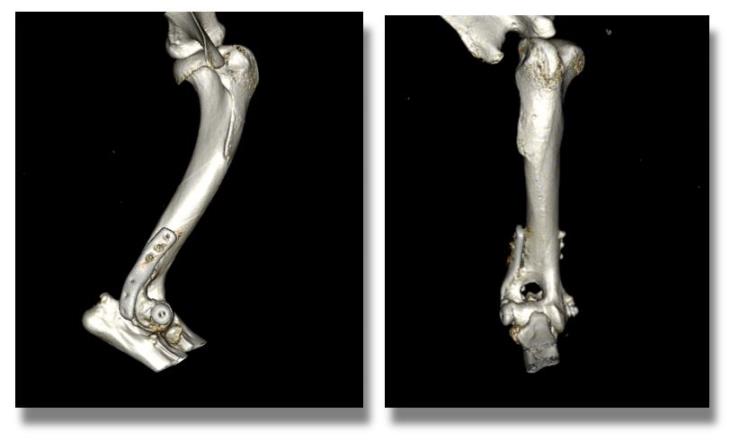

Two months later the patient a further CT scan was performed to assess his progress and we were pleased to confirm excellent osseous union and no implant-associated complications.

He is currently doing well enjoying an active lifestyle and has not required long-term medications nor exercise restriction.